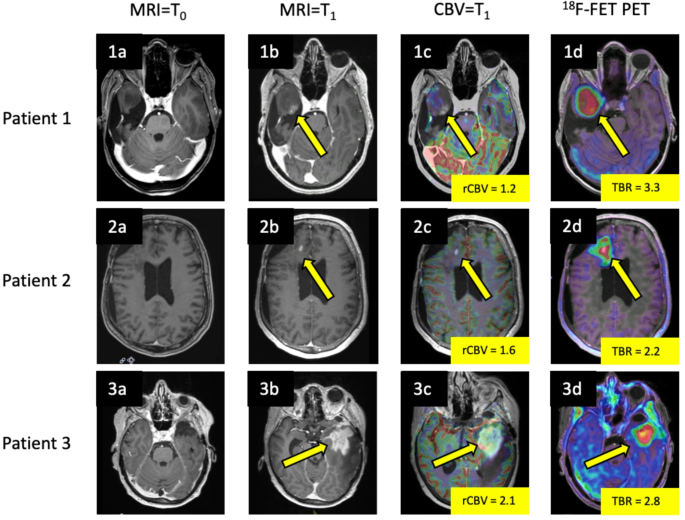

Three different high-grade glioma post-treatment patients with routine follow-up MRI studies demonstrating no contrast enhancement initially (1a, 2a, 3a; all contrast-enhanced T1-weighted images). Upon further MRI follow-up, a new contrast-enhancing lesion was discovered in the right temporal lobe (1b; arrow), right frontal lobe (2b; arrow) and left temporal lobe (3b; arrow). rCBV (relative cerebral blood volume) values derived from Dynamic susceptibility weighted perfusion MRI performed at the time of lesion discovery revealed below-threshold rCBV values for all three patients (1c, 2c, 3c; arrows), suggesting the diagnosis of treatment-related changes. 18F-FET PET performed at the time of MRI = T1 demonstrated high tracer uptake (TBR; tumor to background ratio) and correctly overturned the diagnosis to tumor progression in all cases (1d, 2d, 3d; arrows).

All patients underwent 18F-FET PET scanning. Median time difference between MRI and 18F-FET PET was 27 days (range 2 to 112 days), with MRI being acquired first in 67% (33/49) of cases. Above the MRI threshold of rCBV 2.4, 18F-FET PET classified 20/21 cases correctly as tumor progression and classified one as treatment-related changes (false-negative i.e. true tumor progression determined by gold standard). At or below the threshold of rCBV 2.4, 18F-FET PET reclassified 95% (18/19) MRI rCBV lesions from treatment-related changes to tumor progression (Fig. 2). The remaining 1/19 case was incorrectly classified by both MRI and 18F-FET PET as treatment-related change. All 9 cases of treatment-related change were correctly identified by both MRI and 18F-FET PET. Based on a TBR threshold of 2.1, 43/49 lesions diagnosed by 18F-FET PET were on the appropriate side of the threshold, while for the remaining 6 lesions, the MRI component of the 18F-FET PET/MRI study was given greater weighting. Over the entire cohort, 18F-FET PET demonstrated a sensitivity of 95%, a specificity of 100%, and an AUC of 0.98 (95% CI; 0.94 to 1.00). The sequential, rCBV threshold-based workflow demonstrated a sensitivity of 97%, a specificity of 100%, and an AUC of 0.99 (95% CI; 0.96 to 1.00). Overall, our workflow resulted in a 42.8% (21/49) reduction in the number of 18F-FET PET scans with an NNI of 50.